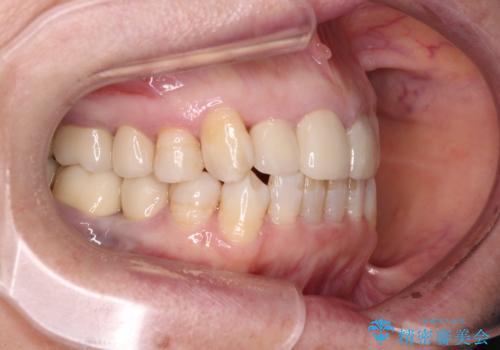

- 全顎的な歯列不正と、銀歯だらけの奥歯を気にして来院された患者様です。

奥歯の銀歯は、セラミッククラウンを装着するには歯の高さが不十分であり、そのままでは矯正治療を行うことが困難であるため、歯冠長延長術を行うこととしました。

また、根管治療の必要な歯がいくつかあるため、歯周外科治療の治癒期間を利用して根管治療を行い、その後インビザラインにて矯正治療を行うこととしました。